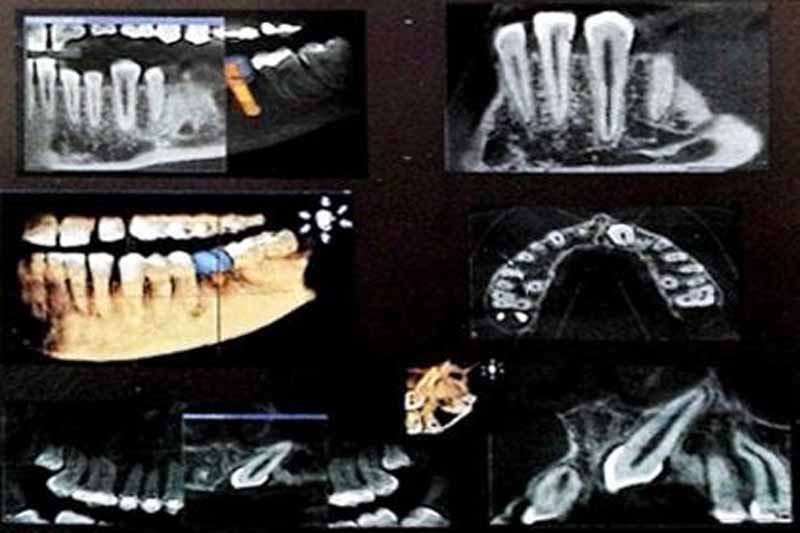

Il Centro Radiologico Di Costanzo di Battipaglia, in provincia di Salerno, si avvale di un efficiente centro di radiologia, recentemente dotato di nuove apparecchiature di Diagnostica per Immagini. La sezione di Radiologia Tradizionale si avvale di apparecchiature moderne con sistema digitalizzato del processo di acquisizione, che consente di ridurre sensibilmente la dose di radiazioni e di rielaborare le immagini acquisite.